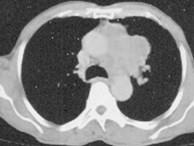

问题 60岁,男,有长期抽烟史,左声带麻痹、声音嘶哑2个月,请结合胸片和CT图,选出最可能的诊断 ( )

选项 A.肺癌 B.肺结核 C.尘肺 D.肺炎 E.肺结节病

答案 A